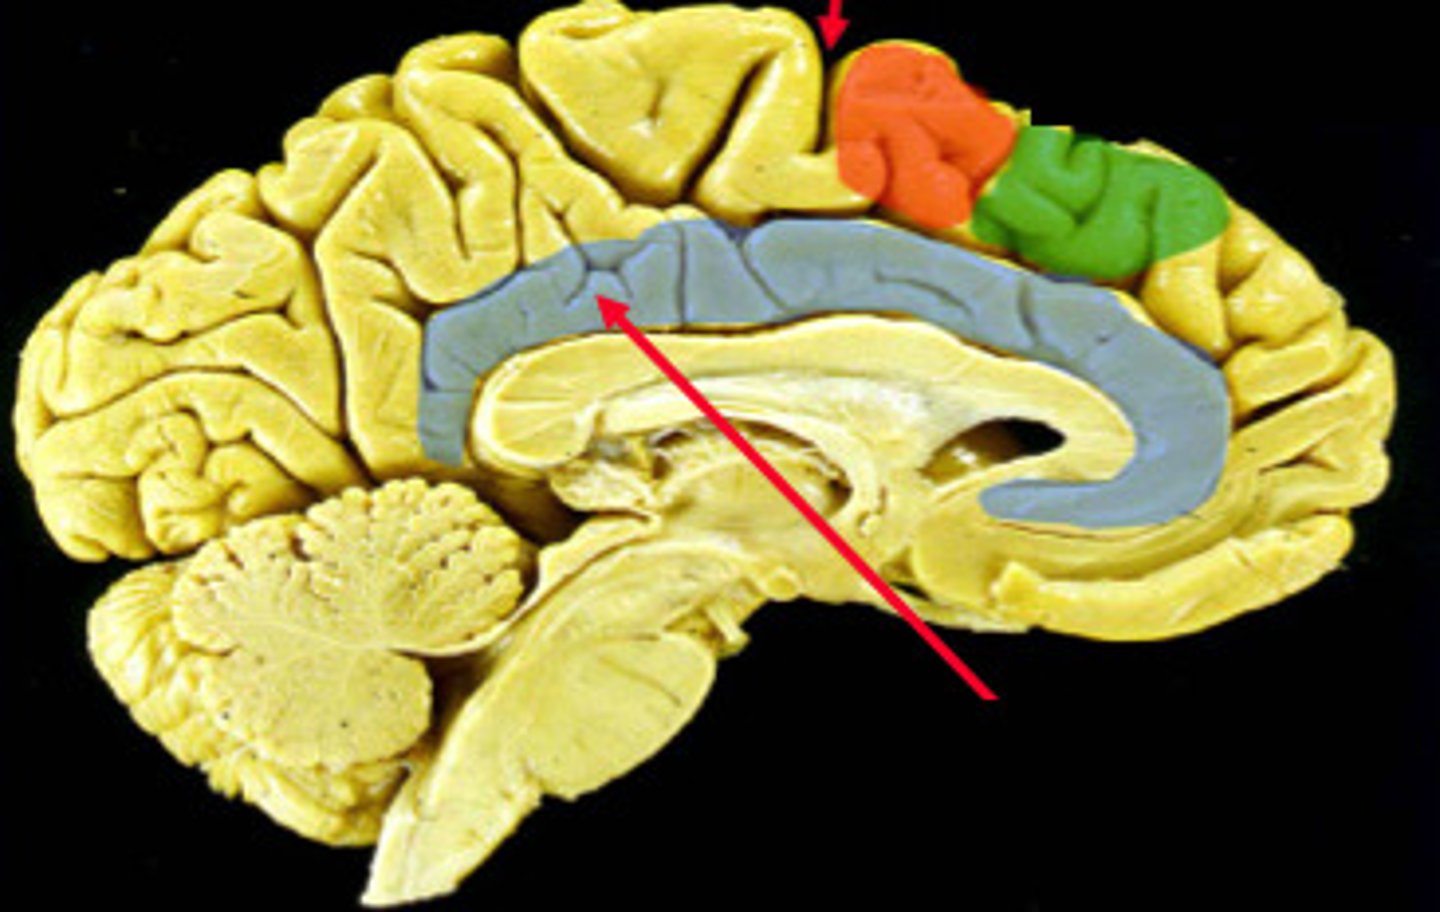

Corpus collosum

Thalamus

Hypothalamus

Corona radiata

corpus callosum

lateral ventricles

3rd ventricle

Thalamus

Hypothalamus

Hippocampus

fornix- a fiber tract that extends from the hippocampus to the mammillary body

Amygdala- fear and aggression

cingulate cortex - emotional and motor processing (cognition)